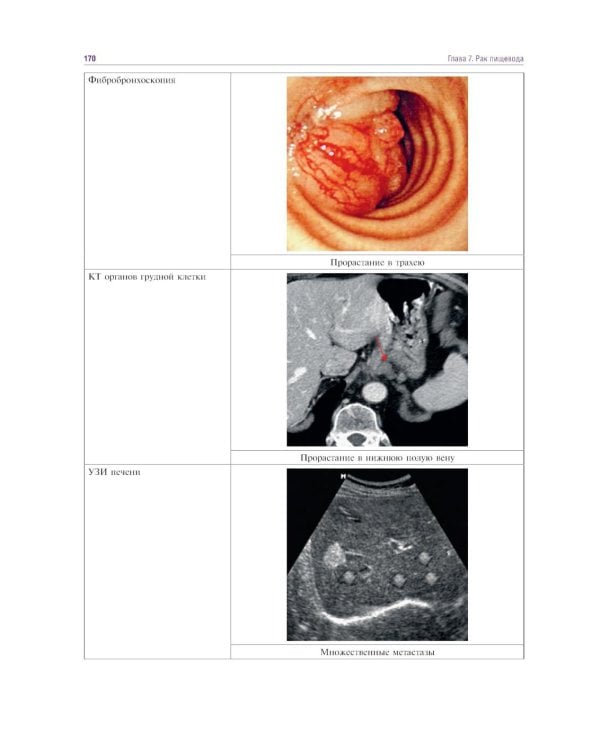

Злокачественные новообразования - распространенная патология в практике врача любой специальности. Рост числа больных указывает на необходимость изучения предмета «Онкология». Главным для студента остается умение клинически осмыслить ситуацию, возникающую у конкретного пациента. В учебном пособии представлены разделы, соответствующие учебной программе. Сведения изложены в краткой форме и позволяют получить информацию о злокачественных новообразованиях ведущих локализаций, их клинических особенностях, факторах риска развития, а также основных способах диагностики и лечения. Логика изложения, оригинальные наглядные схемы, таблицы, фотографии и рисунки, отсутствие больших фрагментов сплошного текста способствуют быстрому и надежному усвоению материала. В конце пособия приведены вопросы тестового контроля знаний и ситуационные задачи, позволяющие студентам самостоятельно проверить уровень подготовки по соответствующей теме. Учебное издание соответствует требованиям федерального государственного образовательного стандарта высшего образования по специальности 31.05.01 «Лечебное дело». Предназначено студентам медицинских вузов, а также интернам, ординаторам, аспирантам и преподавателям кафедр хирургии и онкологии.